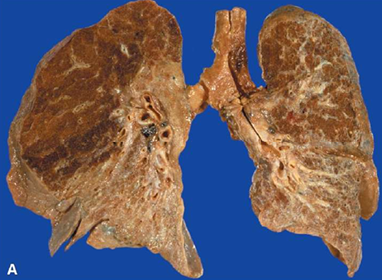

FPI: macro